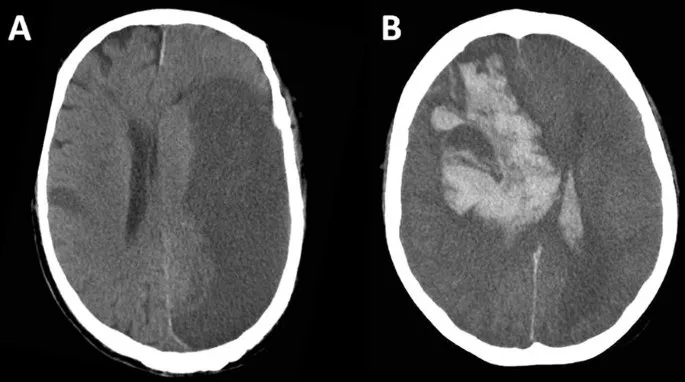

- Hemorrhagic Stroke (ICH):

- Management: BP control (target SBP <140-160 mmHg), reverse anticoagulation.

- Subarachnoid Hemorrhage (SAH): Sudden "thunderclap headache"; non-contrast CT head is initial imaging; nimodipine prevents vasospasm.